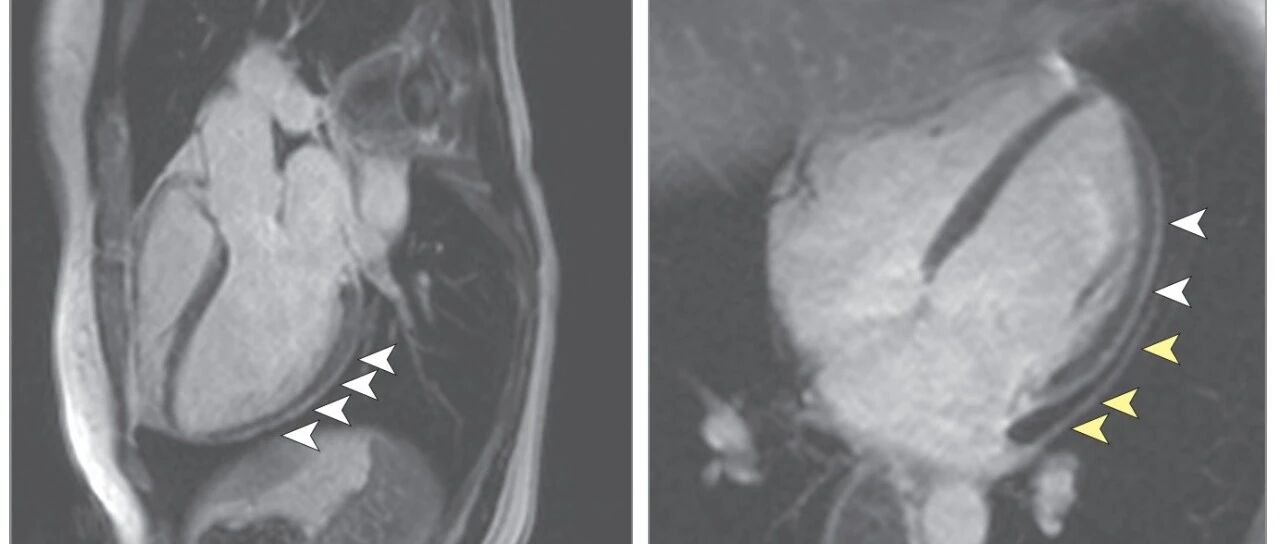

COVID-19康复患者的心血管磁共振成像结果

来源:MedSci梅斯

时间:2020-08-02